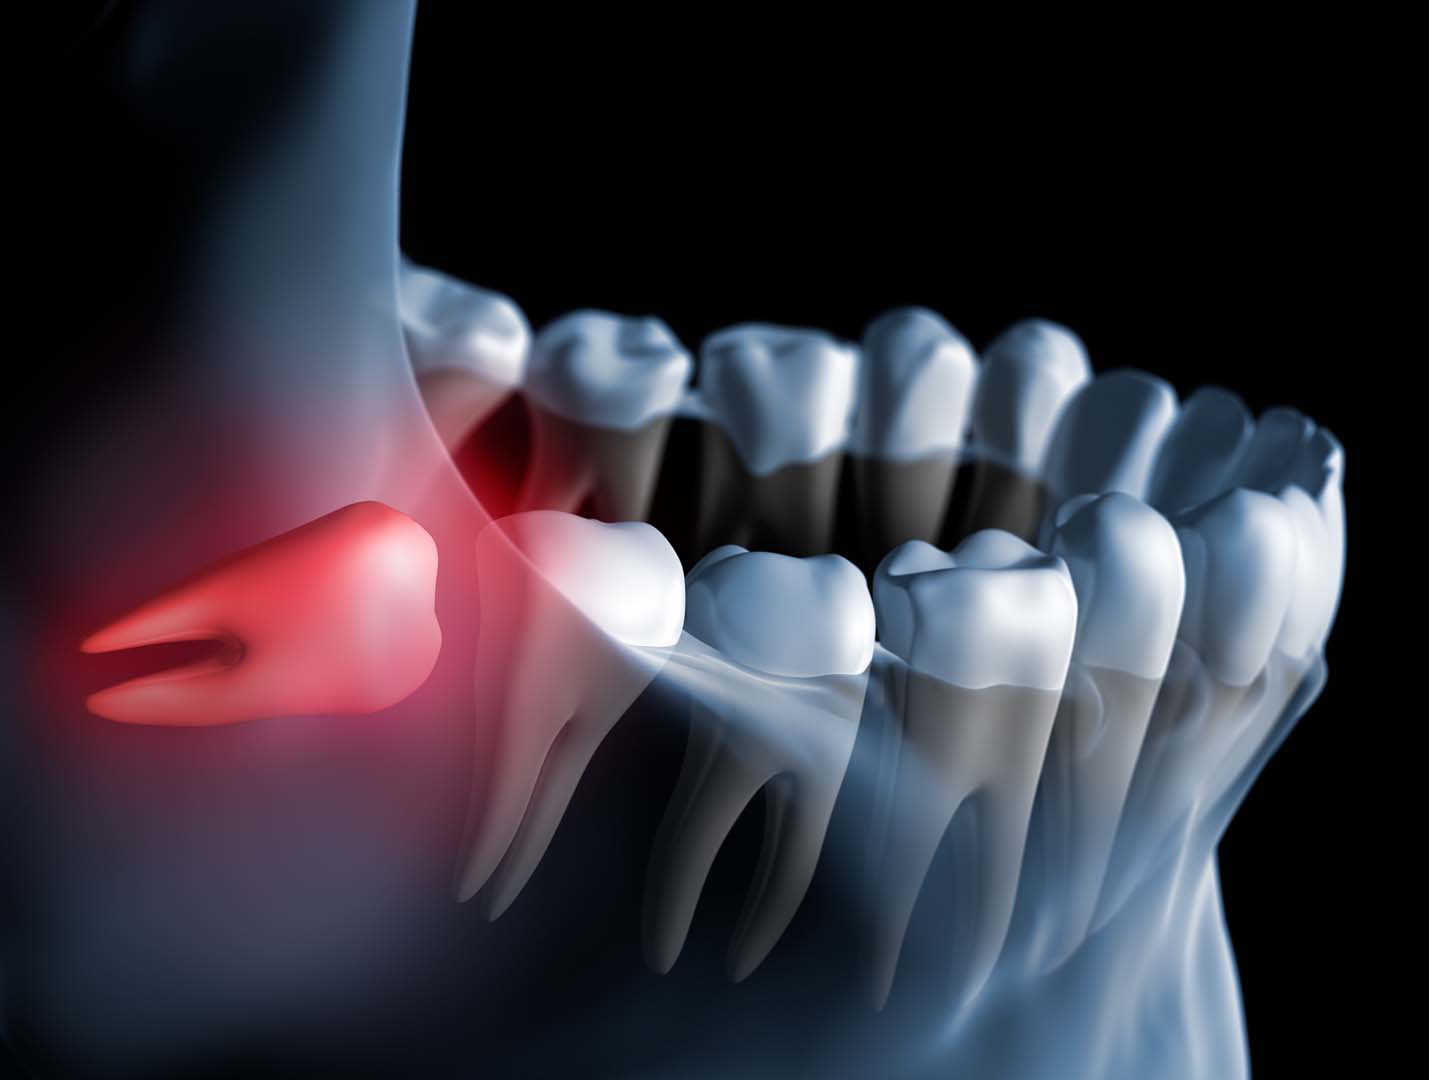

Wisdom teeth are commonly removed because they often don’t have enough room to grow in properly. When they erupt at the wrong angle or remain partially or fully trapped under the gums, they can lead to a range of oral health problems.

- Impaction (tooth is stuck beneath the gums or bone)

- Damage to neighboring teeth